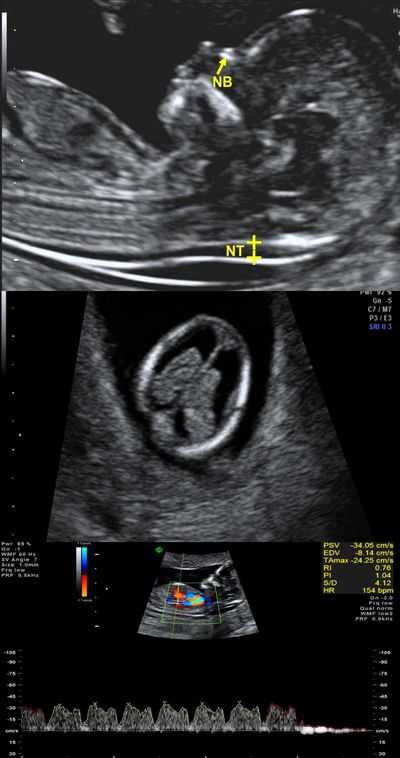

Early Pregnancy Anomaly Scan At 11 13 Weeks Isuog Approved Course Youtube

Best Anomaly Scan In Chennai Anomaly Scan Cost In Chennai Mid Pregnancy Scan In Chennai Gynecologist In Mandaveli Chennai Fertility Hospital In Chennai Ivf Treatment In

Fetal Growth Scan Chennai Growth Scan In Pregnancy Procedure Report Cost

Anomaly Scan In Chennai Anomaly Scan In Anna Nagar Anomaly Scan Near Me Anomaly Scan Price Anomaly Scan In Golden Scans Tiffa Scan In Chennai Tiffa Scan In Anna Nagar Tiffa Scan

Fetal Anomaly Scan Pregnancy Scan Types Of Anomaly Scan Apollo Cradle

Anomaly Scan In Chennai Anomaly Scan Procedure Report Details